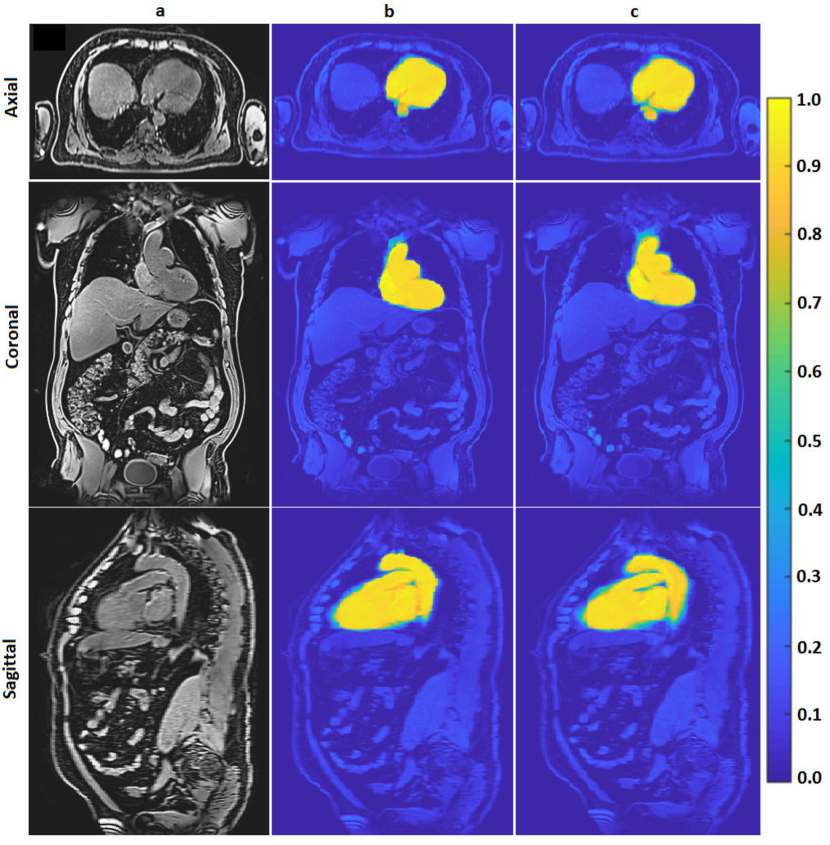

The classification priors of the samples could be estimated by any method such as the multiatlas registration or the hierarchical random forest classifier proposed in [Fallah 2018a, Fallah 2018b, Fallah 2019b, Fallah 2019a]. This happened when the classification probabilities estimated by those methods were not accurate enough to be considered as final classification probabilities (posteriors) rather as initial classification probabilities (priors). For example, the classification probabilities estimated by the proposed forest could not differentiate different kinds of cardiac adipose tissues on fat-water MR images. They could only differentiate the overall adipose tissues from nonadipose tissues. This was due to lack of spatial information in the forest, similar contrasts and features of the cardiac adipose tissues, and weak boundaries between them. The cardiac adipose tissues were spatially close to each other and separated only through thin septa which were hardly detectable under spatial resolution of standard clinical scanners at 3 T. Figure 1 shows voxelwise classification probabilities estimated by the proposed forest for the cardiac adipose tissues and the resulting segmentations on various slices of a fat image. Figure 2 shows overall segmentations of the cardiac adipose tissues based on the voxelwise classification probabilities estimated by the proposed forest on some axial slices of a fat image. Despite inaccuracies of the priors, they, features, and the spatial (neighborhood) relationships of the samples could pave the way for another classifier such as the neighborhood graph to classify the samples more accurately. For example, the priors could approximately localize an addressed object in an image and thereby speed up or reduce the complexity of its accurate segmentation. The more accurate classification probabilities were called the posteriors. Accordingly, the neighborhood graph was supposed to estimate the classification posteriors of every sample (vertex) with regard to its features, its priors, and its spatial (neighborhood) relationships with other samples of the same resolution .

For each pair of source-target images, the overall deformation field, resulting from the aforementioned affine and nonrigid registrations, got diffeomorphically accumulated. Then, this field got applied to the volumetric binary mask of the source image. This way, 10 deformed binary masks were obtained. The deformed masks were overlaid and their overlap percentages got counted in every voxel. If of the deformed binary masks had the value of at a certain voxel, then the probability of this voxel for belonging to the class of cardiac tissue was . This volumetric probabilistic map was called the probabilistic atlas. Figure 11 shows the average and the probabilistic atlases computed for the cardiac structure on 10 water images. By using these computed atlases, the volume of the cardiac structure was segmented on any unseen volumetric water image. To this end, first the final average atlas got registered (deformed) to the unseen image by applying the aforementioned affine and nonrigid registrations. Then, the overall deformation field diffeomorphically accumulated over these registrations got applied to the volumetric probabilistic atlas to form the volumetric probabilistic map of the desired segmentation. Figure 12 compares the probabilistic maps of the cardiac structure estimated by the multiatlas registration and the random forest classifier proposed in [Fallah 2018a, Fallah 2018b, Fallah 2019b, Fallah 2019a] on some slices of a volumetric water image. Figure 13 shows a segmented cardiac structure on some slices of a volumetric water image.